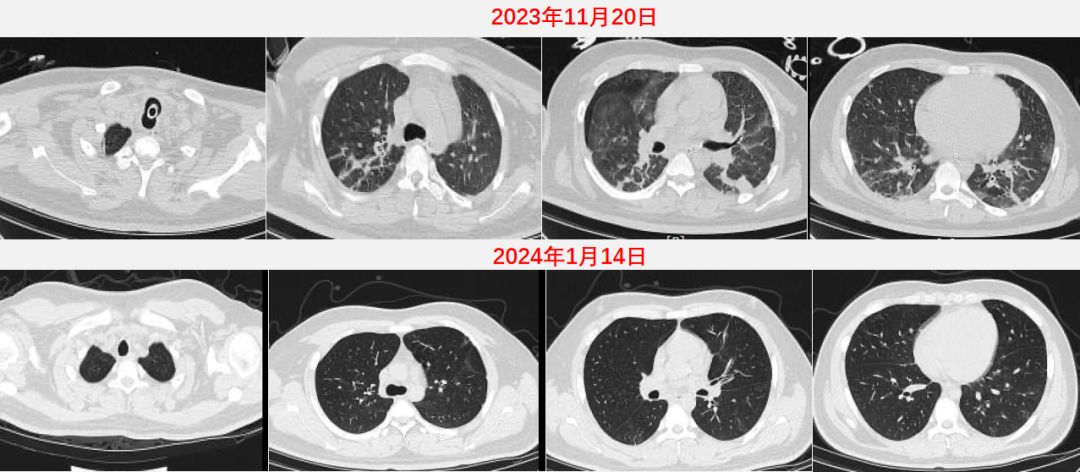

2023年11月20日胸部CT显示窦道形成,2024年1月14日胸部CT可见恢复较好,病变基本吸收(图13)

图片

图13  患者胸部CT